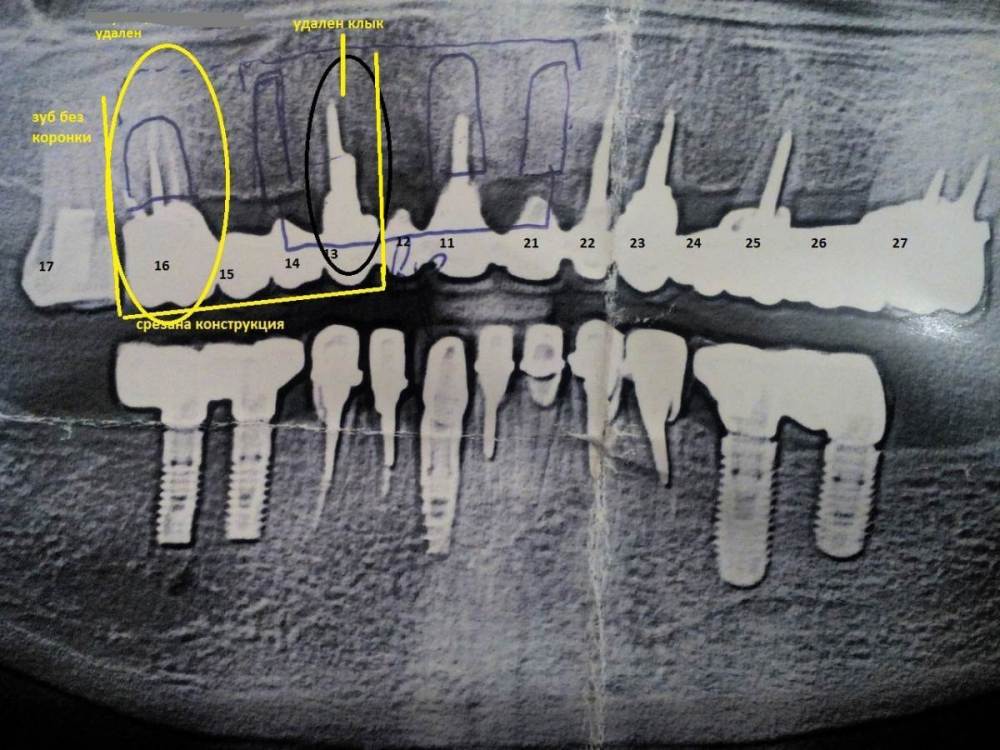

Ольга555 Опубликовано 28 июля, 2023 Поделиться Опубликовано 28 июля, 2023 Предложено полное удаление всех 6 корней и оставшейся мк конструкции, установка 6 имплантов Дентиум и открытый синус лифтинг с 2-х сторон на верхней челюсти. Все в один день. Мне 64 года. Временным, предложен съемный протез с началом изготовления через месяц. Расчет бюджетного протезирования. Смущает временная конструкция,не навредит она? Стоит ли изыскать дополнительные средства и рассмотреть другой способ протезирования на имплантах? И возможно ли вынести в один прием такой объем работы? Снимок 2-х летней давности.С диска КТ пока не знаю как скопировать. Фото эстетического состояния на сегодня.Почти год с отсутствующими. Ссылка на комментарий

Ольга555 Опубликовано 28 июля, 2023 Автор Поделиться Опубликовано 28 июля, 2023 2 года назад,когда мост подал сигнал готовиться к очередному этапу протезирования,как раз делала прикрепленный снимок и КТ для доктора,который ставил этот мост в конце 2010г. А через несколько месяцев он срезал конструкцию из-за образовавшегося флюса клыка(раскачала видимо подвижным мостом) и было новое КТ на половину ,где уже не было конструкции. План протезирования мне озвучил на 2 года работы ,8 имплантов , один синус лифтинг,временные сразу и стоимость почти 600 и предупредил о подорожании после НГ . Пока изыскивала возможности,заболела и кашляла около 3-х месяцев,потом СВО..а я из Курска,переживания что начнем процесс,а заканчивать может и не получится. Теперь боюсь узнать цену у своего прежнего доктора,доллар на взлете. Обратилась в другую частную клинику. Процесс более короткий 6 имплантов,два синус лифтинга открытых и работы чуть более пол года. Конечно трудно найти и принять решение. Ссылка на комментарий